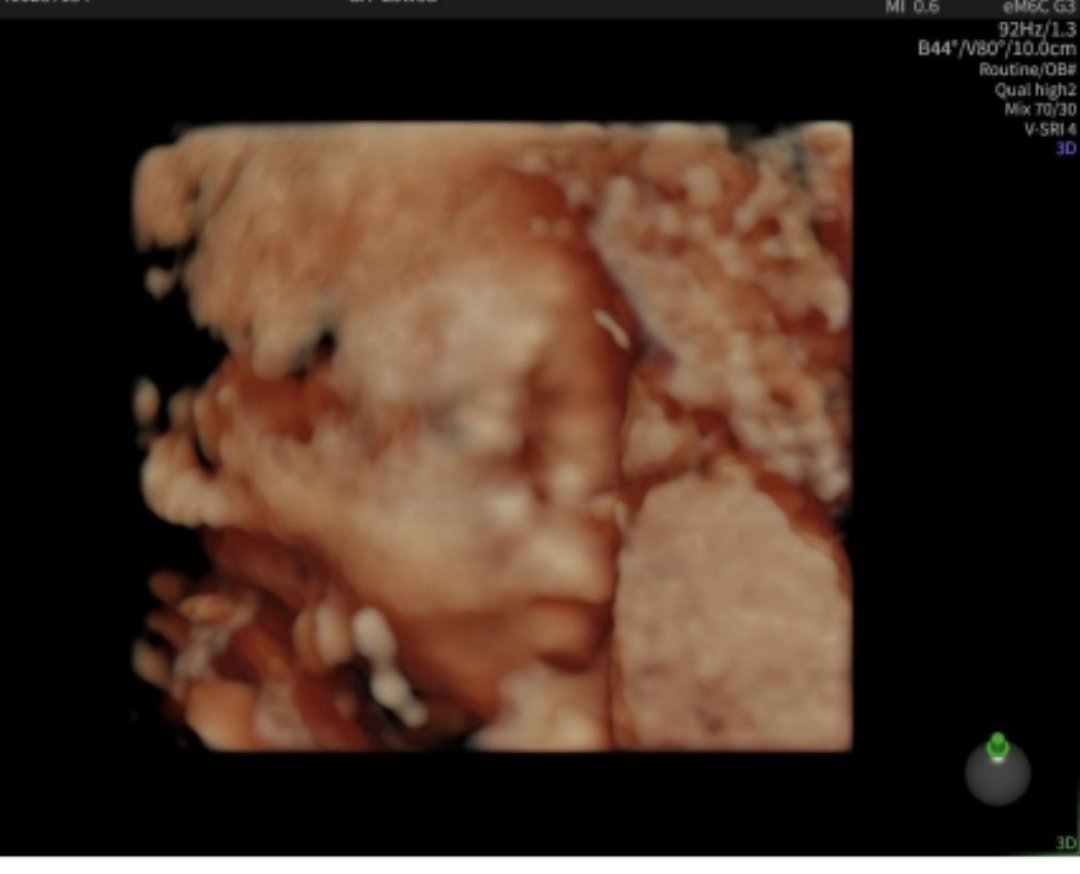

Здравейте момичета! И моята фетална морфология мина днес в 22+5г.с. съм., всичко е наред прегледа продължи около 45-50 мин. гледаха я много обстойно и лекаря каза, че всичко е перфектно. Тежи 550гр. 🩷 Прегледа ми струваше 170лв и бих искала да ви запозная с малката ми Селина 🩷🎀